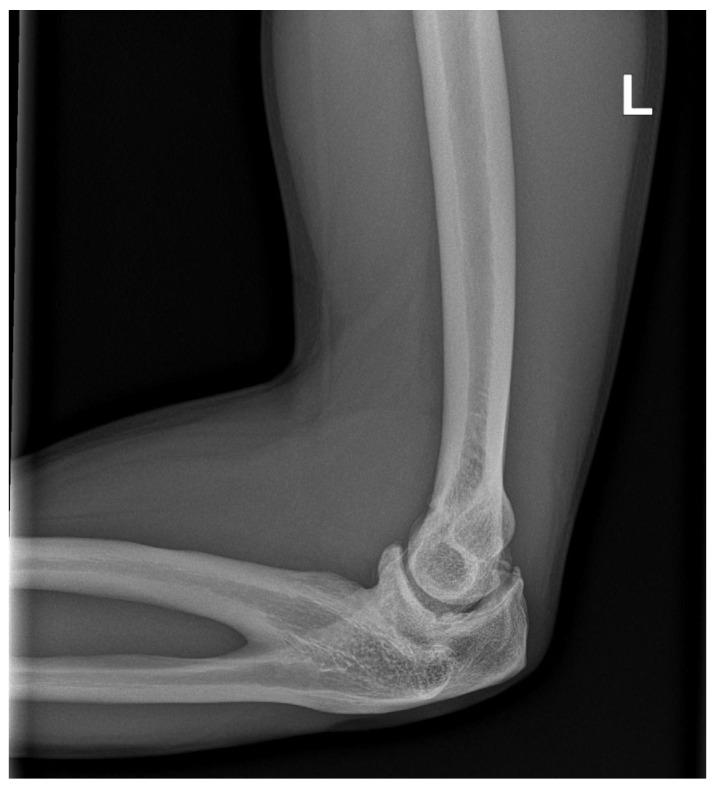

近侧桡尺骨融合(PRUS)是最常见的先天性前臂疾病,尽管其在普通人群中的患病率较低,仅有数百例报道。Pfeiffer、Poland、Holt-Oram 和其他严重的先天性综合征都包含这种异常。非综合征性病例中,孤立的 PRUS 常与 SMAD6、NOG 基因变异或性染色体非整倍体有关。一小部分伴有血液学异常的患者表现为 HOXA11 或 MECOM 基因变异。我们报告了一名非综合征性成年冰球精英运动员,其左侧前臂存在单侧近侧桡尺骨融合。在幼儿时期,他只能像右撇子一样使用曲棍球棒,并且由于缺乏旋后,直到 8 岁才确诊。X 光片显示为 Cleary-Omer Ⅲ型 PRUS,伴有桡骨头发育不良和肱尺关节轻度骨赘退行性变。由于该病症对体育活动的影响极小,因此未考虑手术干预。该运动员继续在顶级水平上从事冰球运动,并加入了国家队参加顶级比赛。问卷调查和体格检查上肢功能评估结果显示,损伤极小。受影响最大的工具是 Failla 评分,总分为 15 分,得分为 10 分。Sanger 测序的基因检测未发现 和 基因中有意义的致病性变异。通过基于阵列的比较基因组杂交未检测到潜在致病性拷贝数变异。在报告的病例中,运动员有能力应对限制前臂旋后功能的解剖变异。如今,通过不断发展的遗传学,可以全面排除更复杂的肌肉骨骼损伤和家族负担。